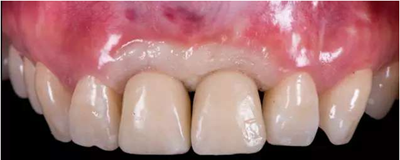

過渡義齒制作完成及試戴

過渡義齒佩戴3個(gè)月后

種植過渡義齒戴牙后1個(gè)月,患者希望改善義齒美觀度,并進(jìn)一步減少唇側(cè)凸度

患者試戴1個(gè)月后,發(fā)現(xiàn)牙齦塑性效果良好,過渡義齒穿齦部分不需要修改

種植過渡義齒戴牙后3個(gè)月,牙齦形態(tài)穩(wěn)定